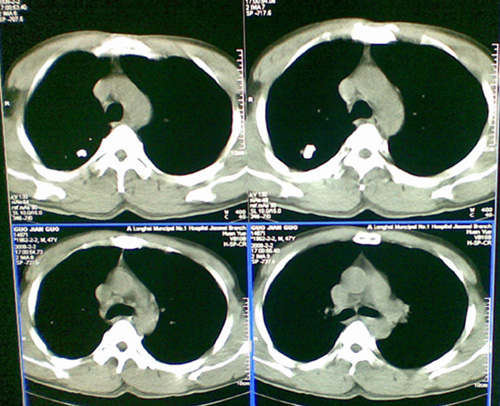

像肺结核钙化吗,不曾见过的影像,请大家帮忙看一下

陈旧性肺结核,钙化。

右肺结核(以纤维增殖、钙化病灶为主)。